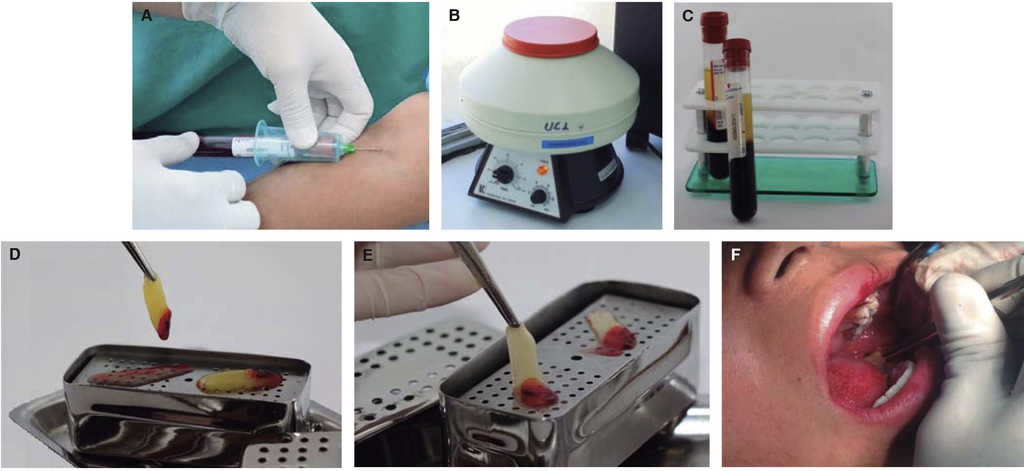

Obtención de PRF

Antes de empezar la extracción quirúrgica se obtuvieron dos muestras de sangre de 10 mL en tubos (BD Vacutainer), cada una para centrifugar a 3,000 rpm durante 10 minutos15 (centrífuga PLC series), no se colocó alguna sustancia anticoagulante. El resultado del centrifugado es llevado a una bandeja para separar el suero de la fibrina durante un minuto. Por último la malla autóloga de fibrina rica en plaquetas fue colocada en el alvéolo postextracción del tercer molar inferior izquierdo (Figura 1).

Figura 1 Proceso de obtención y colocación de PRF. A) Obtención de muestra de sangre. B) Colocación de los tubos en la centrífuga. C) Tubos centrifugados después de tiempo establecido. D) Filtrado del plasma y moldeado de la fibrina. E) Resultado final, fibrina rica en plaquetas (PRF). F) Colocación de PRF en el alvéolo del tercer molar inferior izquierdo.